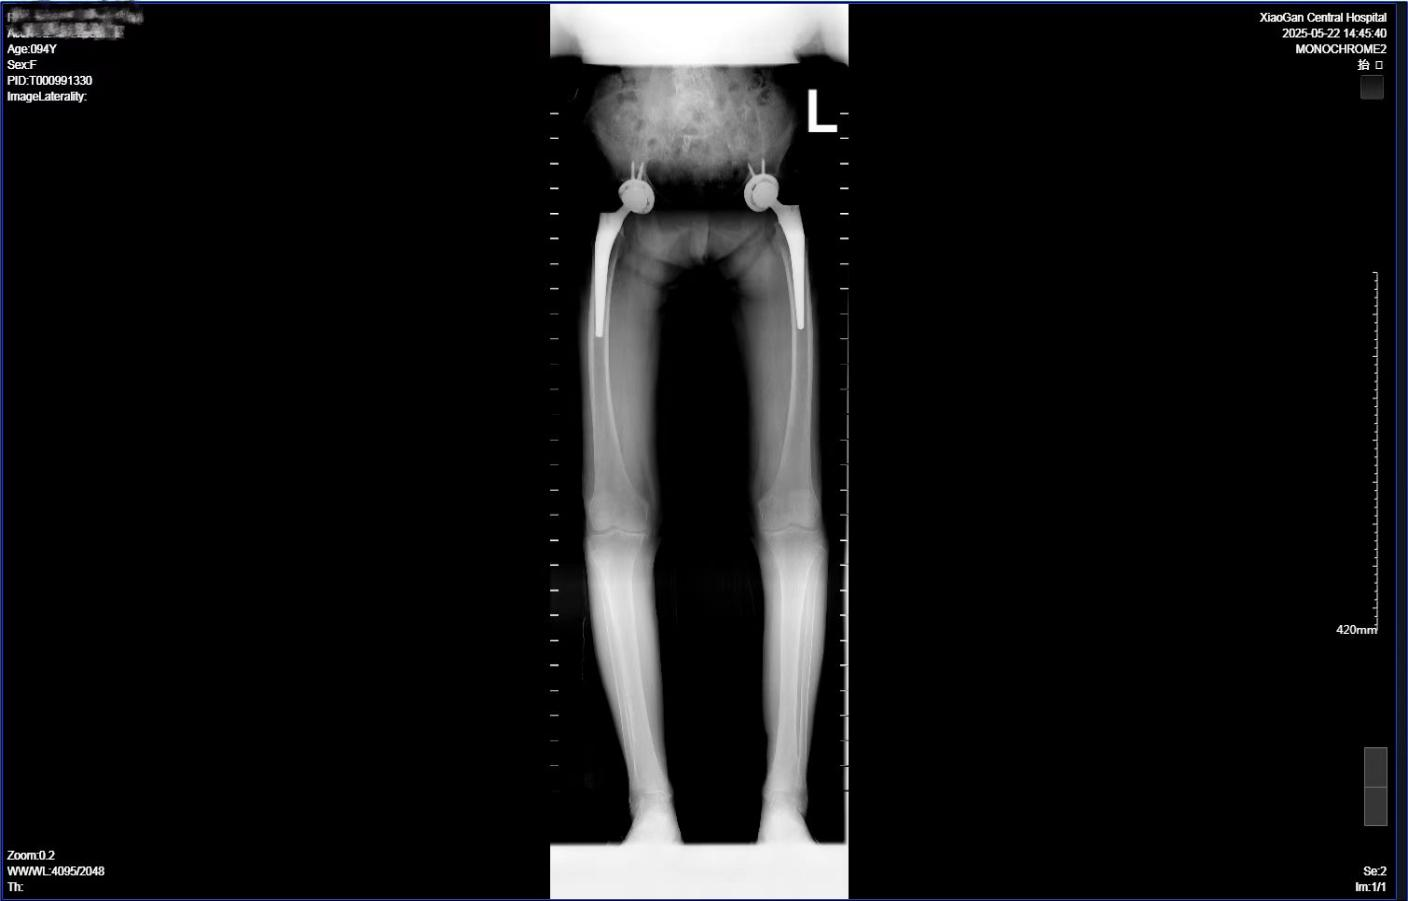

荊楚網(湖北日報網)訊( 通訊員張艷、陳晶)近日,孝感市中心醫院骨科Ⅰ關節病區成功為一位94歲的患者實施了左側全髖關節置換術,為高齡患者的關節疾病治療帶來了新的希望。

一年前,楊奶奶因右側股骨頭壞死導致髖關節疼痛、活動受限,嚴重影響日常生活,遂前往孝感市中心醫院骨科Ⅰ關節病區行右側全髖關節置換手術,術后不僅恢復了自主行走能力,生活質量顯著提升,更重拾了晚年生活的信心。

為了確保手術的成功,骨科Ⅰ關節病區的醫護團隊聯合營養科、內分泌科、呼吸科、麻醉科和心內科等多個學科,進行了全面的術前評估和多學科會診(MDT)。通過精準的風險評估,團隊為楊奶奶制定了個性化的麻醉方案和圍術期管理方案,力求將手術風險降到最低。在充分的準備下,5月19日,手術團隊成功為楊奶奶實施了左側全髖關節置換術。

依托醫院骨科Ⅰ關節病區成熟的快速康復體系,醫護團隊在術前、術中、術后全流程貫徹ERAS(快速康復)理念:術前通過健康宣教緩解患者焦慮,優化營養狀態,指導患者預康復;術中精準操作減少組織損傷;術后通過多模式鎮痛、早期康復介入及個性化護理,最大程度降低并發癥風險。在醫護團隊的密切配合下,楊奶奶術后第一天即拔除引流管,并在護士的指導下使用助行器穩步行走,刷新了高齡患者術后康復的“加速度”,患者術后第5天已出院。

從“高風險人群”到術后次日穩健邁步的“康復奇跡”,94歲楊奶奶的診療歷程,不僅是醫學技術對高齡禁區的勇敢突破,更是多學科協作與人文關懷交織的溫暖篇章。她的“雙髖新生”,見證了市中心醫院以患者為中心的精準醫療體系如何將風險化為機遇,讓耄耋之年的生命依然能從容行走、尊嚴生活。